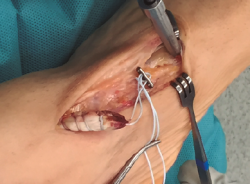

Figura 5. Inserción de la placa metálica a través del túnel óseo.

Se realiza túnel con broca de 4,5 mm al nivel de la cortical dorsal de la cuña medial con oblicuidad de proximal a distal hasta llegar a la cortical plantar (Figura 4). Posteriormente, se ensancha el mismo al nivel de la primera cortical según el diámetro del tendón tibial anterior, utilizando una pinza gubia o un avellanador.

Figura 6. Tracción de los hilos para deslizar el tendón tibial anterior en el túnel óseo.

Se procede a la introducción de la placa al nivel del túnel transóseo hasta empujarla fuera de la cortical plantar (Figura 5). Posteriormente, se introduce el tendón en el túnel de la cuña mediante la tracción de los hilos (Figura 6). En este paso resulta útil en ocasiones embocar con ayuda de un mosquito el tendón a la entrada del túnel óseo.

Figura 7. Anudado con ayuda de un empujahilos.

Finalmente, se realiza el anudado de la sutura sobre el sistema de fijación con ayuda de un empujanudos (Figura 7).

Figura 8. Aspecto final de la reinserción transósea del tendón tibial anterior.

Una vez finalizado este paso, se asegura la estabilidad del sistema mediante la flexoextensión del tobillo (Figura 8) y se comprueba con fotoescopia la correcta colocación de la placa metálica al nivel de la cortical plantar de la cuña medial (Figura 9).